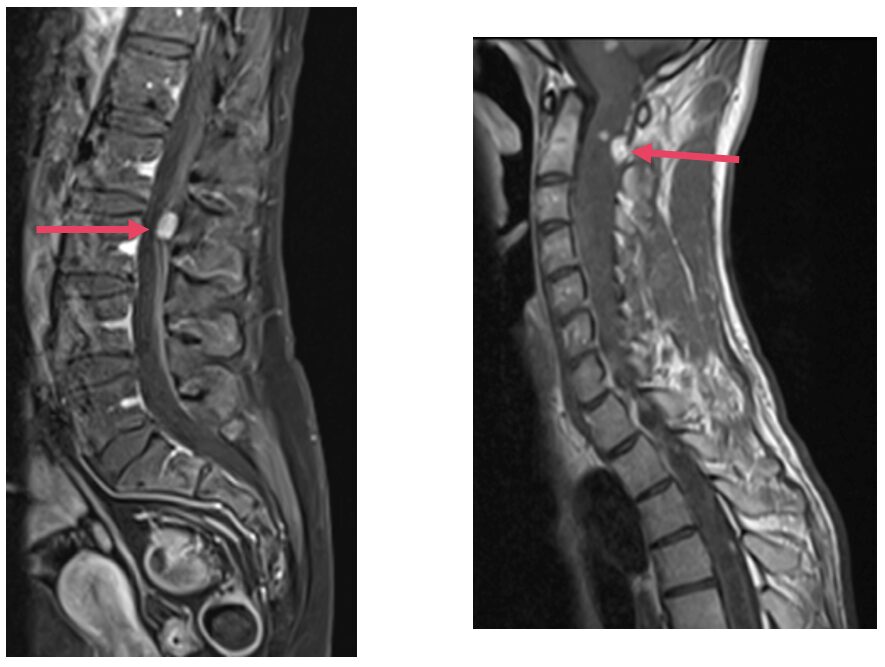

Les tumeurs rachidiennes sont des tumeurs bénignes ou malignes situées dans la colonne vertébrale (=rachis). Elles peuvent se situer dans la moelle épinière ou dans le canal médullaire.

Le diagnostic passe par des examens d’imagerie telle que le scanner ou l’IRM.